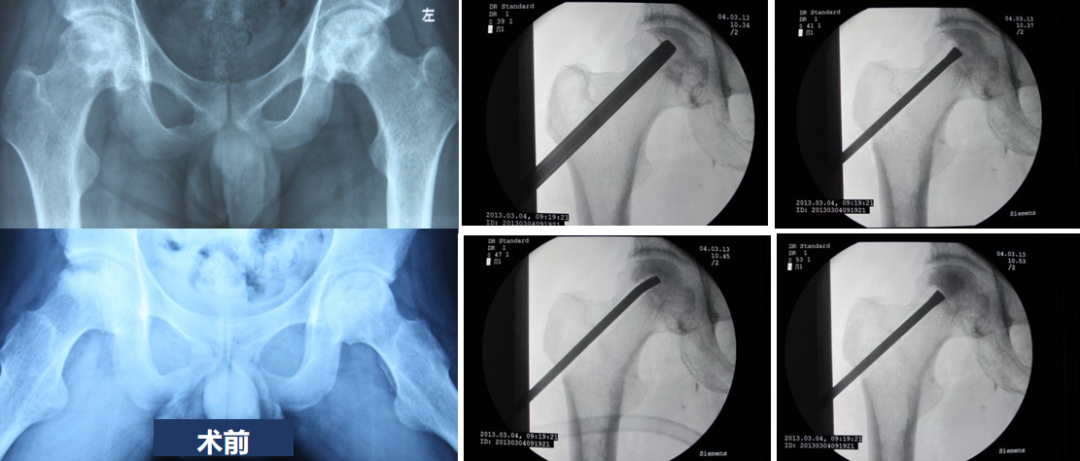

2.微创髓芯减压病灶清除植骨术

术前X片可见双侧股骨头均为JIC C1型,外侧壁部分保留,坏死病灶见片状透亮影,予行髓芯减压植骨术

术后随访可见坏死病灶片状硬化,修复良好,外侧壁增厚,股骨头形态保持良好